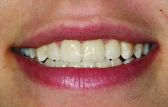

FIGURE 29--Final case 4 vibrant veneers.